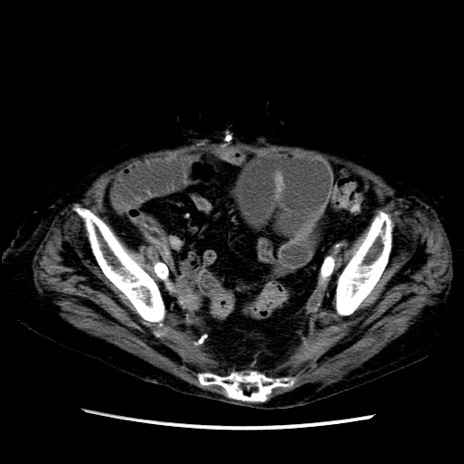

症例14(横断像)

【症例】 90歳代女性

【主訴】 腹痛・嘔吐

【現病歴】今朝から左側腹部痛を認めた。 経過観察していたが、嘔吐を認めたため来院。

【既往歴】 子宮癌術後

【身体所見】 意識清明、BP 127/54mmHg、P 98bpm Sp02 95%(RA)、BT 35.8°C、腹部平坦・軟腸ぜん動音聴取良好、右下腹部圧痛(+) 反跳痛なし

【データ】WBC 9800、CRP 0.46